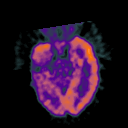

Glioma Overlay -- Slice #7

[Home][Help][Clinical] Slice 7